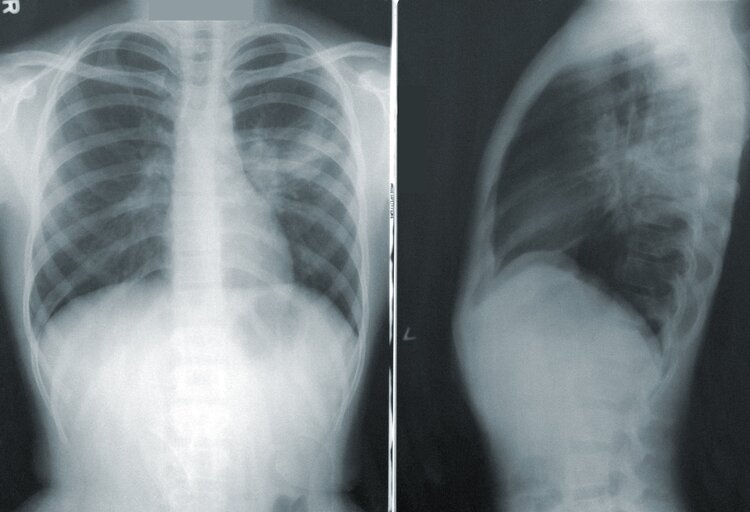

On your first visit, we will do a thorough history, a detailed examination, x-rays (if necessary and warranted), and we will begin with gentle pain-relieving therapeutic modalities such as electrical muscle stimulation. We will not do an adjustment on your first visit, because we need time to review your x-rays prior to doing any adjustments.

During your second visit, we will show you the x-rays taken on the first visit and discuss the findings of the examination. We will also present our recommendations for your course of treatment. After this discussion, we will begin with the first adjustment, and will likely do further pain-relieving therapeutic modalities.